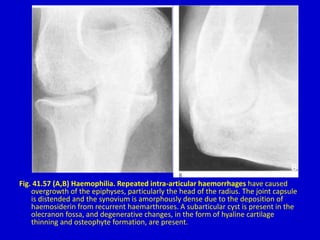

Fig. 41.57 (A,B) Haemophilia. Repeated intra-articular haemorrhages have caused

overgrowth of the epiphyses, particularly the head of the radius. The joint capsule

is distended and the synovium is amorphously dense due to the deposition of

haemosiderin from recurrent haemarthroses. A subarticular cyst is present in the

olecranon fossa, and degenerative changes, in the form of hyaline cartilage

thinning and osteophyte formation, are present.

Fig. 41.57 (A,B)Haemophilia. Repeated intra-articular haemorrhages have caused overgrowth of the epiphyses, particularly the head of the radius. The joint capsule is distended and the synovium is amorphously dense due to the deposition of haemosiderin from recurrent haemarthroses. A subarticular cyst is present in the olecranon fossa, and degenerative changes, in the form of hyaline cartilage thinning and osteophyte formation, are present.